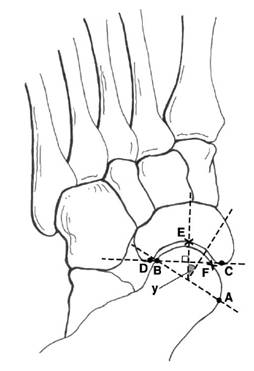

距舟覆盖角 1. 距骨关节面最内侧A,最外侧B,取两者连线 2. 舟骨关节面最内侧C,最外侧D,取两者连线 3. 两条直线垂线的夹角即为距舟覆盖角 – 正常人平均:10°(14°) – 扁平足平均:≥22

距骨第2跖骨角 1. 距骨颈取两条平行线,其中点的连线A 2. 第2跖骨轴线B – 正常足:<16°(3-6°) |